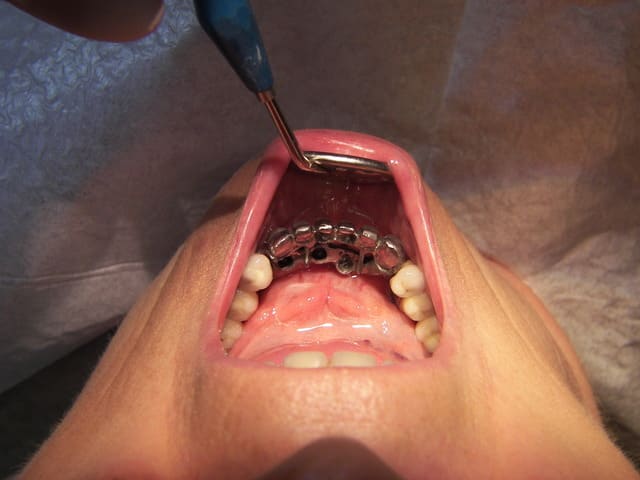

Pxav, faut changer de fil...

C'est IC + couronne (assez peu intéressant...)

Là, ton truc sur implants, c'est bien de voir quelques choses de différents !

T'aurais pas du placer les implants si lingual !

;-))

C'est drôle, j'ai fais un truc du genre hier (plus simple)